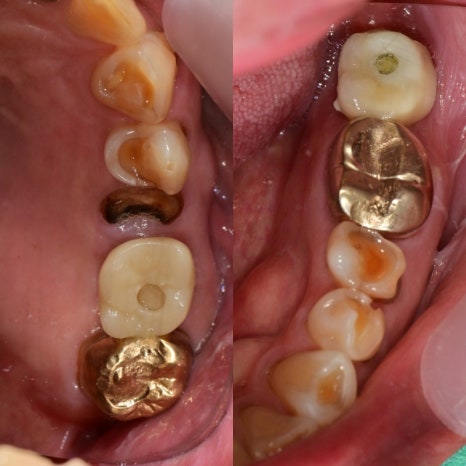

구강 내 사진입니다. 왼쪽 2개의 사진이 치료한 사진, 오른쪽 2개의 사진이 치료 후 사진입니다.

기존 치아들은 지르코니아 보철물로 회복이 되었고, 보험 임플란트는 교합면의 힘을 지지해 줄 수 있는 메탈 교합면을 선택했습니다.

마모된 치아의 외형을 복원함으로써 위아래 어금니의 균형 잡힌 교합을 완성 시켜줄 수 있어 4개의 어금니에 균일한 교합력을 부여하였습니다.